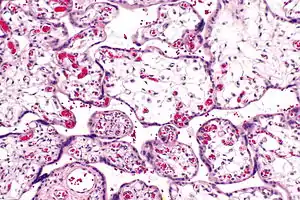

| Micrograph of villous immaturity. H&E stain. | |

Immature chorionic villi are larger and have more central blood vessels; thus, the diffusion distance for gas and nutrient exchange is larger and, therefore, placental function is impaired.

Low mag.